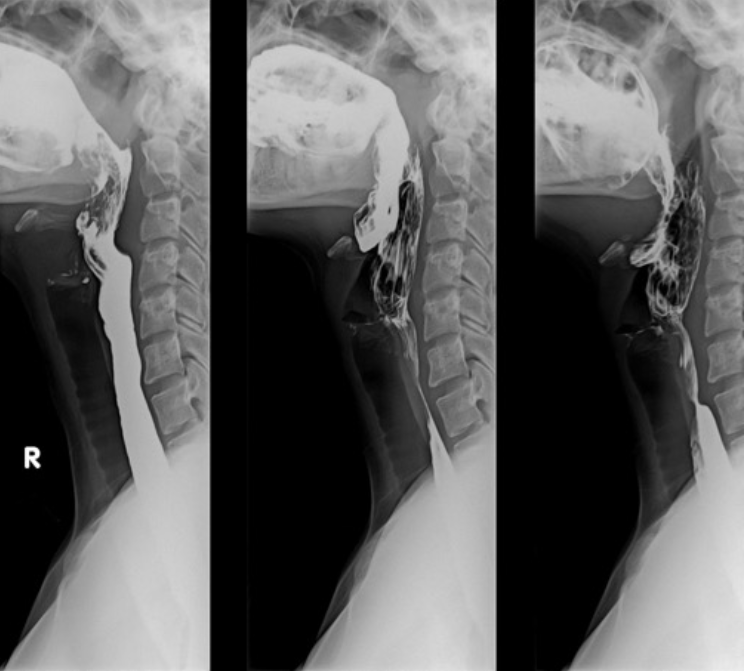

Upper GI Series (Barium swallow)

What imaging is used to assess for esophageal stricture or dysphagia (difficulty swallowing), may include fluoroscopy?

Which imaging can be fluoroscopy (real time) or radiographs?

-barium swallow: dysphagia, esophageal stricture